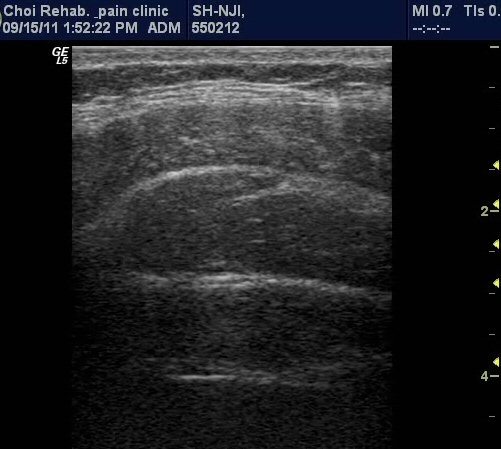

¹è²Å ¿ÜÃø¿¡ ÆÀÃËÀÚ¸¦(ŽÃËÀÚ 1) ´ë°í º¹±ÙÀ» °üÂûÇÔ ¸ð½À, ¼¼ÃþÀÇ º¹±ÙÀÌ °üÂûµÇµµ

°¡Àå ½ÉºÎ¿¡ Ⱦº¹±ÙÀÌ °üÂûµÇ°í ÀÖ´Ù(±×¸² 1). ¼Òº¯À» ÂüÀ¸¼¼¿ä, °ñ¹ÝÀ» ¸Ó¸®ÂÊÀ¸·Î ¿Ã¸®¼¼¿ä,

¹è²ÅÀ» ¹Ù´ÚÀ¸·Î ³»¸®¼¼¿ä µîÀ¸·Î À¯µµÇÑ »óÅ¿¡¼­ Ⱦº¹±ÙÀÇ µÎ²²°¡ µÎ²¨¿ö Áø »óÅÂ(±×¸² 2, 3,

µ¿¿µ»ó 1, 2). ŽÃËÀÚ¸¦ Ä¡°ñ »óºÎ(ŽÃËÀÚ 2)¿¡ ´ë°í ¹æ±¤À» °üÂûÇÑ »óÅ¿¡¼­ °ñ¹Ý ¹Ù´ÚÀÇ ±ÙÀ°À»